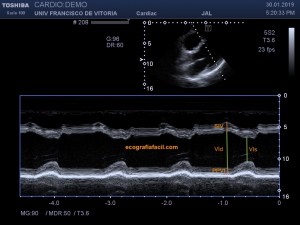

139. Ecocardiografía. Estudio Paraesternal Eje Largo.

141. Mediciones de los planos paraesternales.